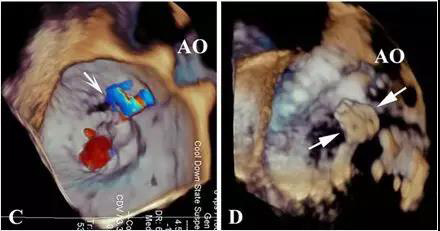

怎么办?再次开胸体外循环手术患者难以耐受,可能意味着死亡,风险更大。而再次经胸封堵术需要去堵“铆钉”间的缝隙,漏口小,对医生的难度大、风险大。有导丝无法通过漏口、捅掉以前植入的封堵器,术后仍然有残余漏、溶血等风险。顶着巨大的压力,李红昕和郭文彬带领的医疗团队经过认真的讨论、分析,决定依据心尖入路比较直的特点,改经左胸-心尖途径去封堵“铆钉”间的缝隙。术中,他们利用自主发明的直中空探条输送系统,成功将导丝送过两个伞盘的间隙,分别再次植入一枚特质封堵器,共4枚,完全封堵住了MPVL。术后患者血红蛋白尿、贫血、黄疸消失,肝肾功能恢复正常,痊愈出院。

经胸MPVL封堵,全部在三维超声引导下操作,解剖图像清晰,患者和医务人员不接触X线和造影剂;中空探条输送系统短,操作灵活,封堵MPVL成功率高。有关该技术的文章已于今年发表于世界顶级心胸外科杂志《Ann Thorac Surg》上。三位患者的成功表明:经右胸或左胸途径微创封堵MPVL能克服传统介入治疗的不同难点,已逐步走向成熟,成为治疗二尖瓣瓣周漏的又一利器,为患者解除了再手术痛苦,为心外科医生解除了后顾之忧。